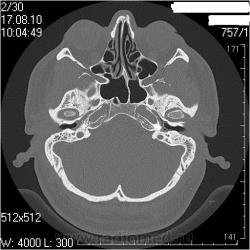

Правая височная кость

Наружный слуховой проход: конфигурация обычная, просвет не сужен, костные стенки ― ровные, четкие.

Сосцевидный отросток: тип строения склеротический, в сохранившихся ячейках отмечаются снижение прозрачности за счет патологических структур.

Воздушные полости среднего уха: пневматизация нарушена полностью за счет мягкотканных (41едН) патологических структур; размеры аттика, адитуса и антрума в пределах нормы. Ширина аттика ― 5,6мм (N=6.4-7мм), адитуса ― 2,1мм (N=3,1-3,3мм), антрума ― 4,6 мм.

Костное устье слуховой трубы: заполнено мягкотканными патологическими структурами.

Слуховые косточки прослеживаются

Внутреннее ухо: размер, форма, положение, плотность и контуры элементов структур внутреннего уха не изменены.

Внутренний слуховой проход: конфигурация не изменена, контуры ровные, четкие, ширина ― 3,2мм (N=4-6мм)

Левая височная кость

Наружный слуховой проход: конфигурация обычная, просвет не сужен, костные стенки ― ровные, четкие.

Сосцевидный отросток: тип строения склеротический.

Воздушные полости среднего уха: пневматизация нарушена за счет пристеночных мягкотканных (41едН) патологических структур; размеры аттика, адитуса и антрума в пределах нормы. Ширина аттика (на уровне латерального канала) ― 5,7мм (N=6.4-7мм), адитуса ― 3,5мм (N=3,1-3,3мм), антрума ― 6,4мм.

Костное устье слуховой трубы: пристеночные мягкотканные патологические структуры.

Слуховые косточки прослеживаются

Внутреннее ухо: размер, форма, положение, плотность и контуры элементов структур внутреннего уха не изменены.

Внутренний слуховой проход: конфигурация не изменена, контуры ровные, четкие, ширина ― 4,3мм (N=4-6мм)

Заключение: КТ- признаки двустороннего хронического среднего отита: склеротические изменения больше выражены в левом сосцевидном отростке; мягкотканные патологические структуры в воздушных полостях среднего уха больше выражены справа; блок костного устья правой слуховой трубы; неполный блок костного устья левой слуховой трубы